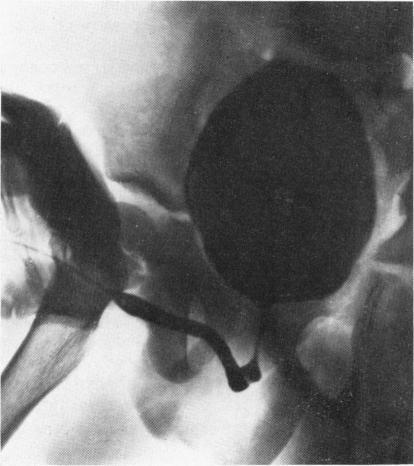

FISHER O D, FORSYTHE W I

Arch Dis Child. 1954 Oct;29(147):460-71. doi: 10.1136/adc.29.147.460.